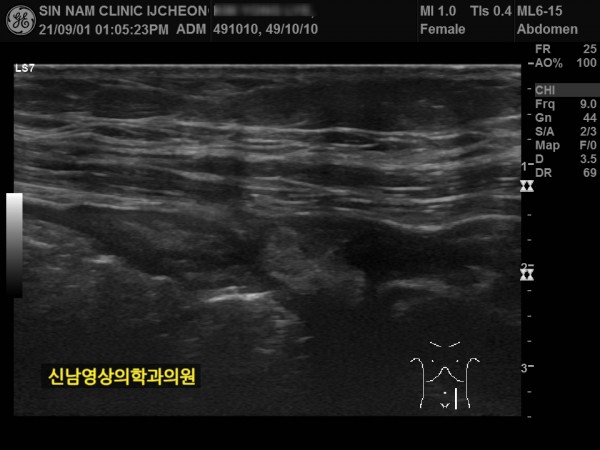

1년 뒤 수술 부위에 탈장이 발생하셔서 탈장 수술을 받으셨던 분입니다.